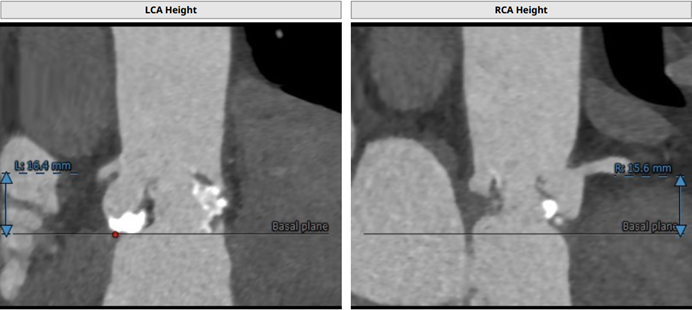

左冠开口高度:16.4 mm;右冠开口高度:15.6 mm

左冠高度高度:14.6mm

右冠高度高度:9.8mm